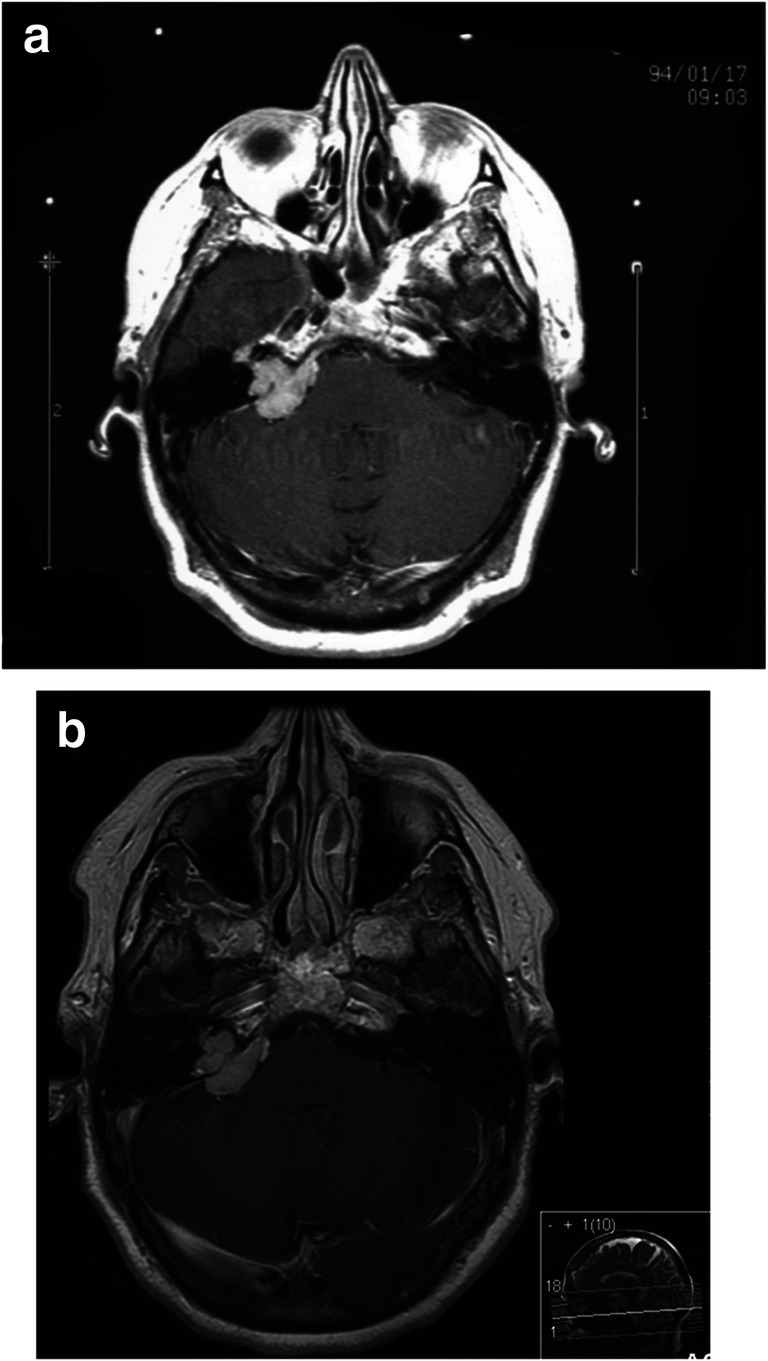

Fig. 3.

a Gamma Knife treatment of petrous meningioma with clival extension. b Follow-up 15 years after Gamma Knife treatment with virtually unchanged volume of the meningioma